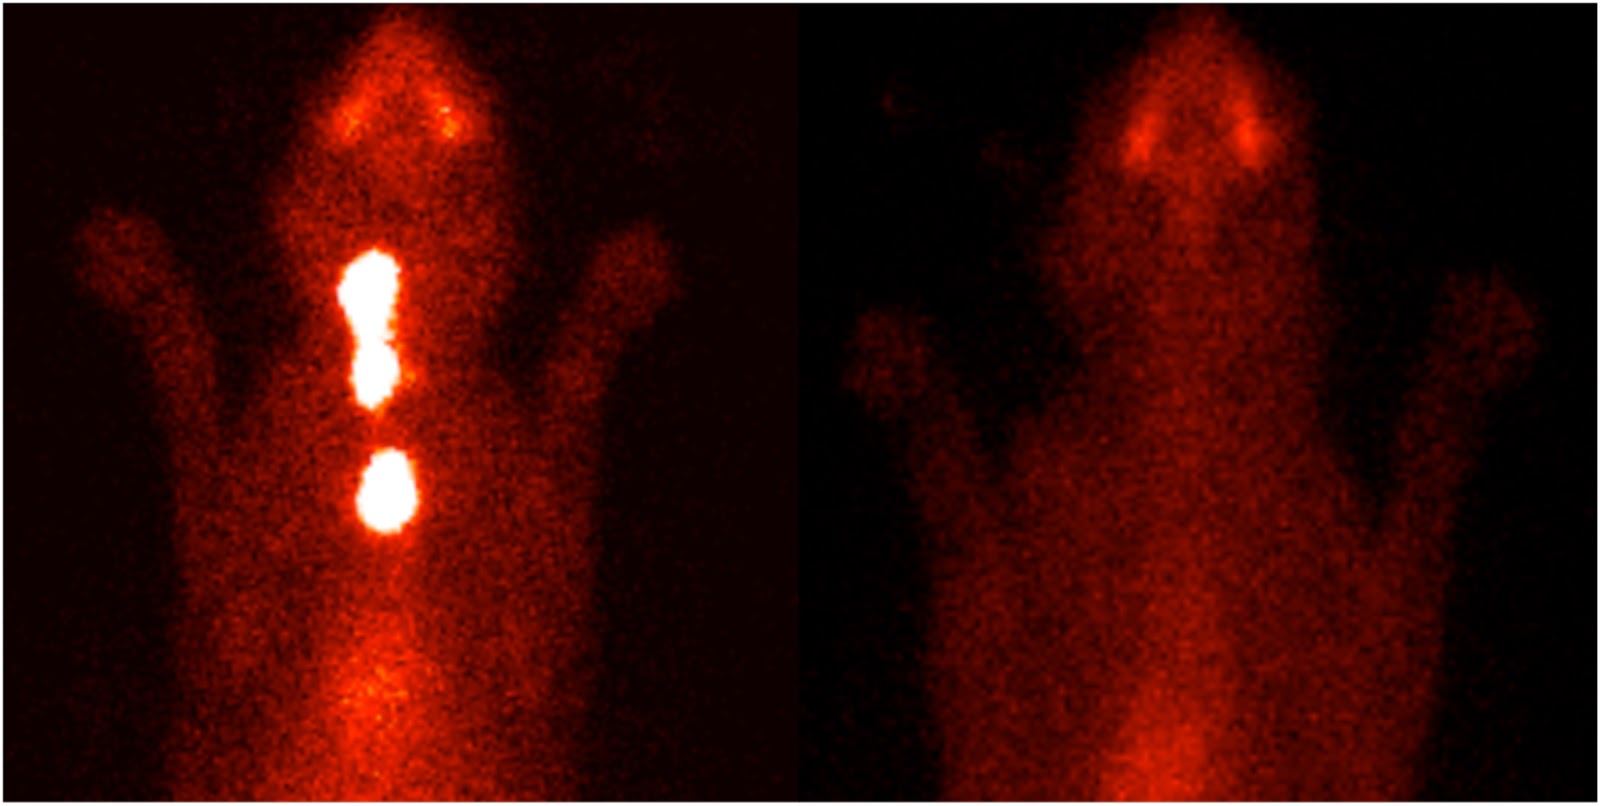

Animal Endocrine Clinic Thyroid Scintigraphy for Diagnosis and Staging Thyroid Removal Surgery In Cats Because this hormone controls many organs, it can lead to multiple. Once the cat has been screened for concurrent problems and thyroid levels have been brought into the normal range, then surgery can. Hyperthyroidism is when thyroid glands work overtime and produce too much thyroid hormone. You will be familiar with the. Surgical removal (thyroidectomy) of the diseased lobes of. Thyroid Removal Surgery In Cats.